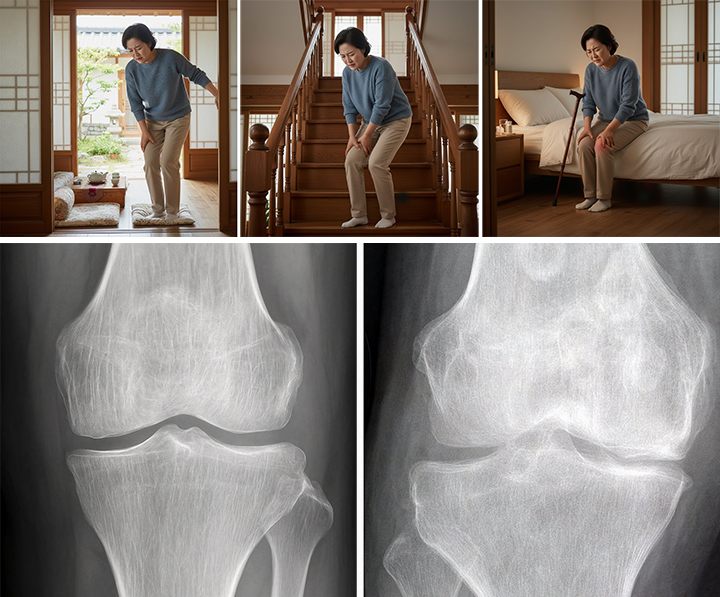

2. 단계별로 보는 무릎 통증의 특징

▷ 초기 단계

ㆍ아침에 일어날 때 무릎이 뻣뻣함

ㆍ오래 앉았다가 움직일 때 불편함

ㆍ걷다 보면 점차 풀리는 느낌

ㆍ뚜렷한 붓기나 열감은 없는 경우가 많음

이 단계에서는 연골 손상보다

관절 주변 근육·인대 기능 저하와 관절 환경 변화가 통증의 주된 원인인 경우가 흔합니다.

▷ 중기 단계

ㆍ계단 오르내릴 때 통증

ㆍ외출이나 활동 후 무릎이 묵직하거나 붓는 느낌

ㆍ통증이 며칠 이상 반복됨

ㆍ활동량이 점차 줄어듦

이 시기부터는 연골 변화와 함께

활막염이 반복되며 통증 빈도와 강도가 증가하는 양상이 나타납니다.

▷ 말기 단계

ㆍ휴식 중이나 야간에도 통증

ㆍ보행 거리 감소, 절뚝거림

ㆍ지속적인 부종과 관절 변형

ㆍ영상에서 관절 간격 감소가 뚜렷한 경우

이 단계에서는 통증 조절과 기능 유지가 치료의 중심이 됩니다.